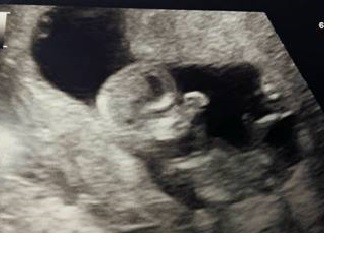

Cudowne zdjęcieBabeczki ale jestem szczęśliwaSześć lat i warto było czekać dla tego zdjęcia

Zobacz załącznik 792406

Babeczki ale jestem szczęśliwaSześć lat i warto było czekać dla tego zdjęcia